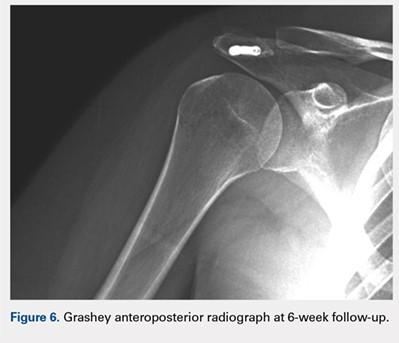

At her second visit (6 weeks), she was completely pain free. Clinical examination showed no tenderness at the acromion, healed incisions, and pain-free passive ROM. Radiographs demonstrated early evidence of consolidation and no sign of fixation failure (Figures 6-8). Her Single Assessment Numeric Evaluation (SANE) score was 85%, and her Simple Shoulder Test (SST) score was 3/12. She was permitted to discontinue the sling, to begin using the arm actively at the side, and progress with unloaded use above shoulder height over the next 6 weeks.